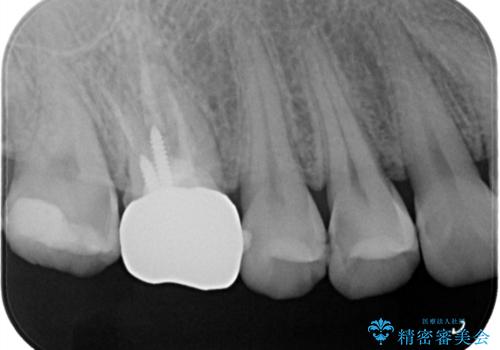

- 右上4、5間にフロスのひっかかりがあり、レントゲンから隣接面う蝕を確認しました。う蝕除去後は両歯にCADCAMインレーをセットしています。